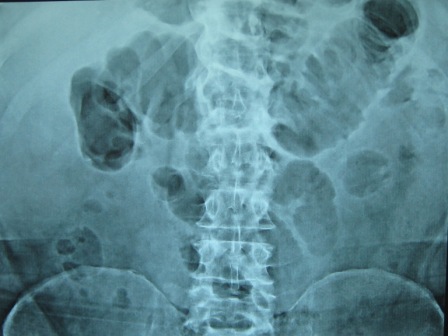

This report is about two cases of acute abdomen-like symptoms that proved to be due to swine flu. Two patients above 60 years of age, with cardiac and respiratory chronic disease, presented with acute abdominal pain. One of them was subjected to abdominal exploration that revealed functional colonic obstruction. The diagnosis of H1N1 was made later upon development of respiratory symptoms. In the other case the diagnosis of H1N1 was made preoperatively, and conservative management was pursued. Once H1N1 was suspected, viral culture was performed and found positive. Acute abdominal symptoms were relieved in both cases by administration of Oseltamivir. Acute abdomen-like presentation of H1N1 Influenza is rare. Suspecting such a diagnosis is crucial to save patients with an H1N1 Acute abdomen-like presentation unnecessary surgery. Cure of the patient and prevention of disease spread depend on accurate diagnosis of H1N1. Surgeons should be aware of the possibility of presentation with acute abdomen-like symptoms, during an H1N1 outbreak.Downloads